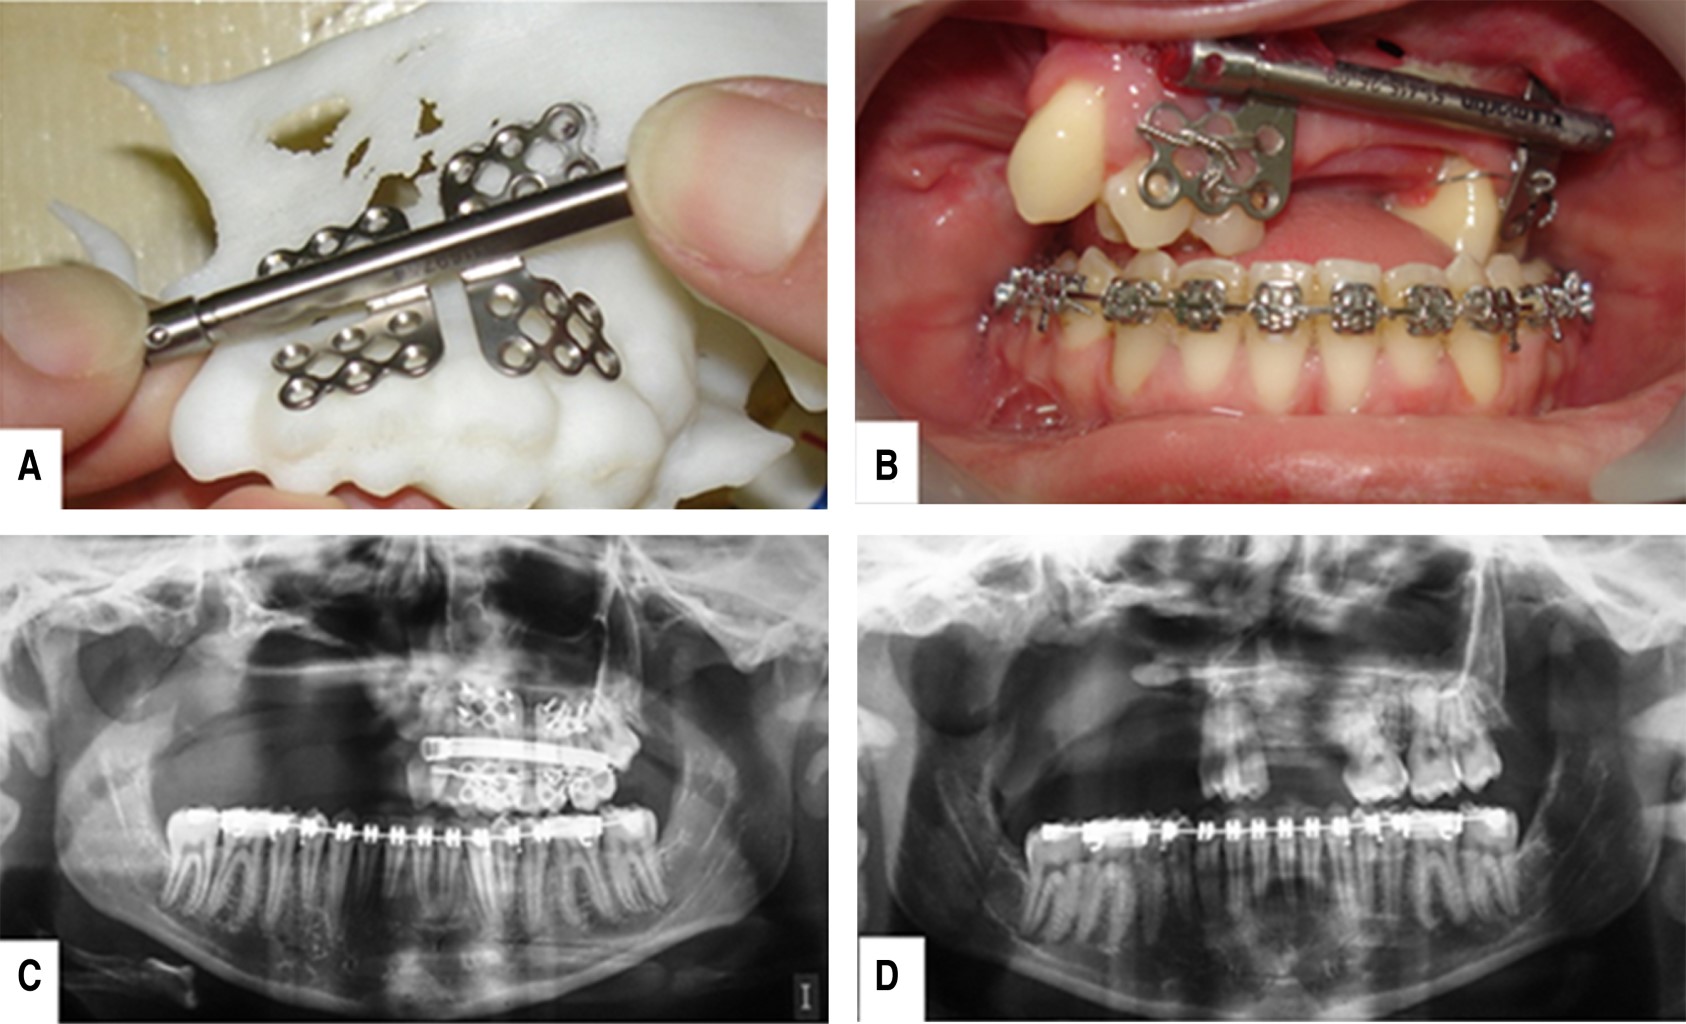

Figure 3